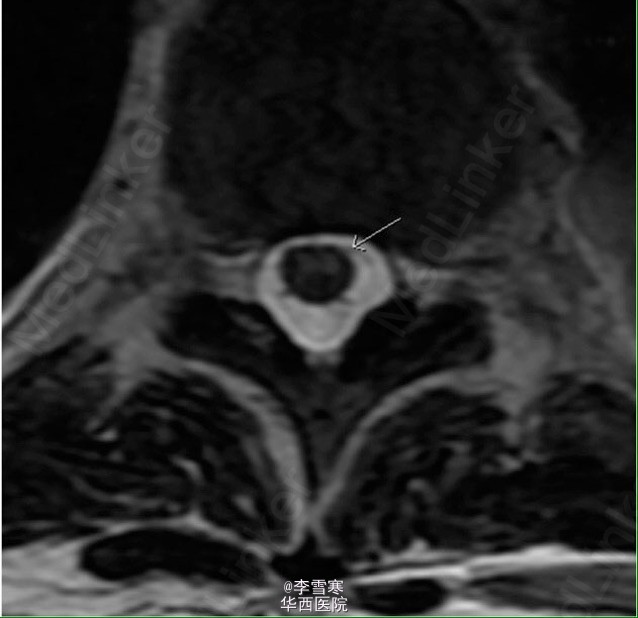

胸膜外全肺切除术后脊髓缺血

患者肺部活检为恶性胸膜间皮瘤,行胸膜外全肺切除术,术中两次低血压,术后第二天双下肢不能动弹,仅存知觉。转自网络